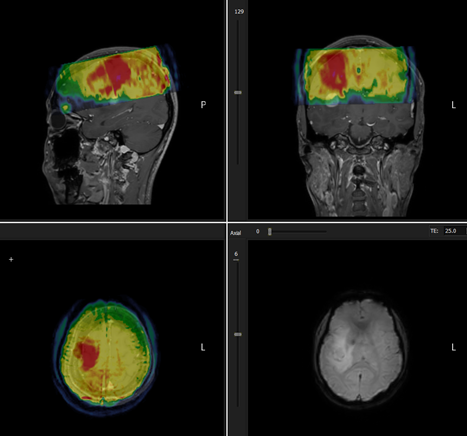

This

will load the perfusion series as overlay on the structural MPR series:

Figure 1: Visualization of poor coregistration between perfusion

and structural series